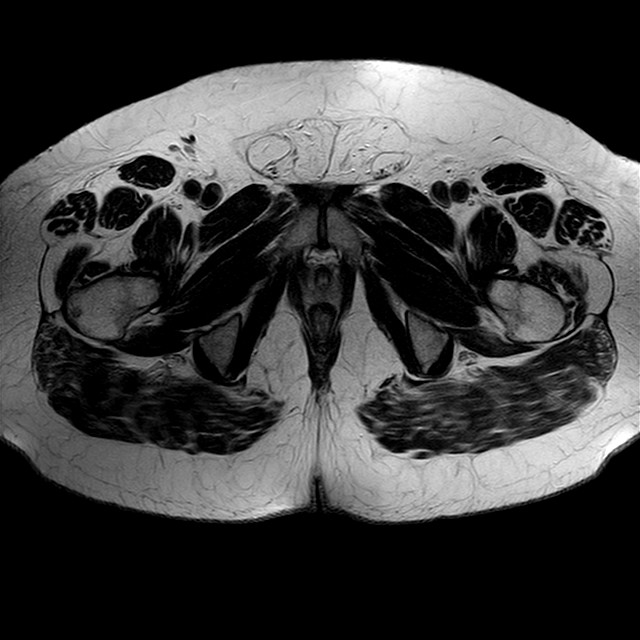

Esami: RMN BACINO

eT2w TSE

Evidenti e simmetriche alterazioni osteofitosiche in regione coxo femorale con riduzione delle rime articolari. Degenerazione completa del cercine glenoideo. Non attuali segni di versamento articolare. Non segni di edema osseo che escludono attuale algodistrofia od osteonecrosi. Lieve e simmetrica riduzione del trofismo della muscolatura glutea.